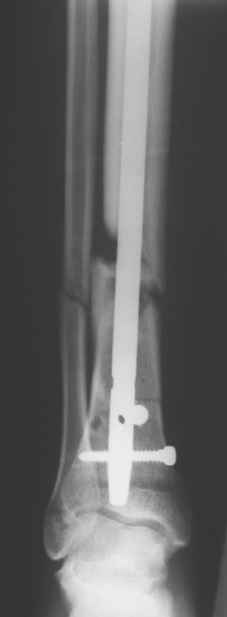

Сегодня прооперировали без открывания. Хотел-бы услышать комментарии по поводу послеоперационной нагрузки.

Имя     : Прямой.JPG

Имя     : Прямой дистальный.JPG